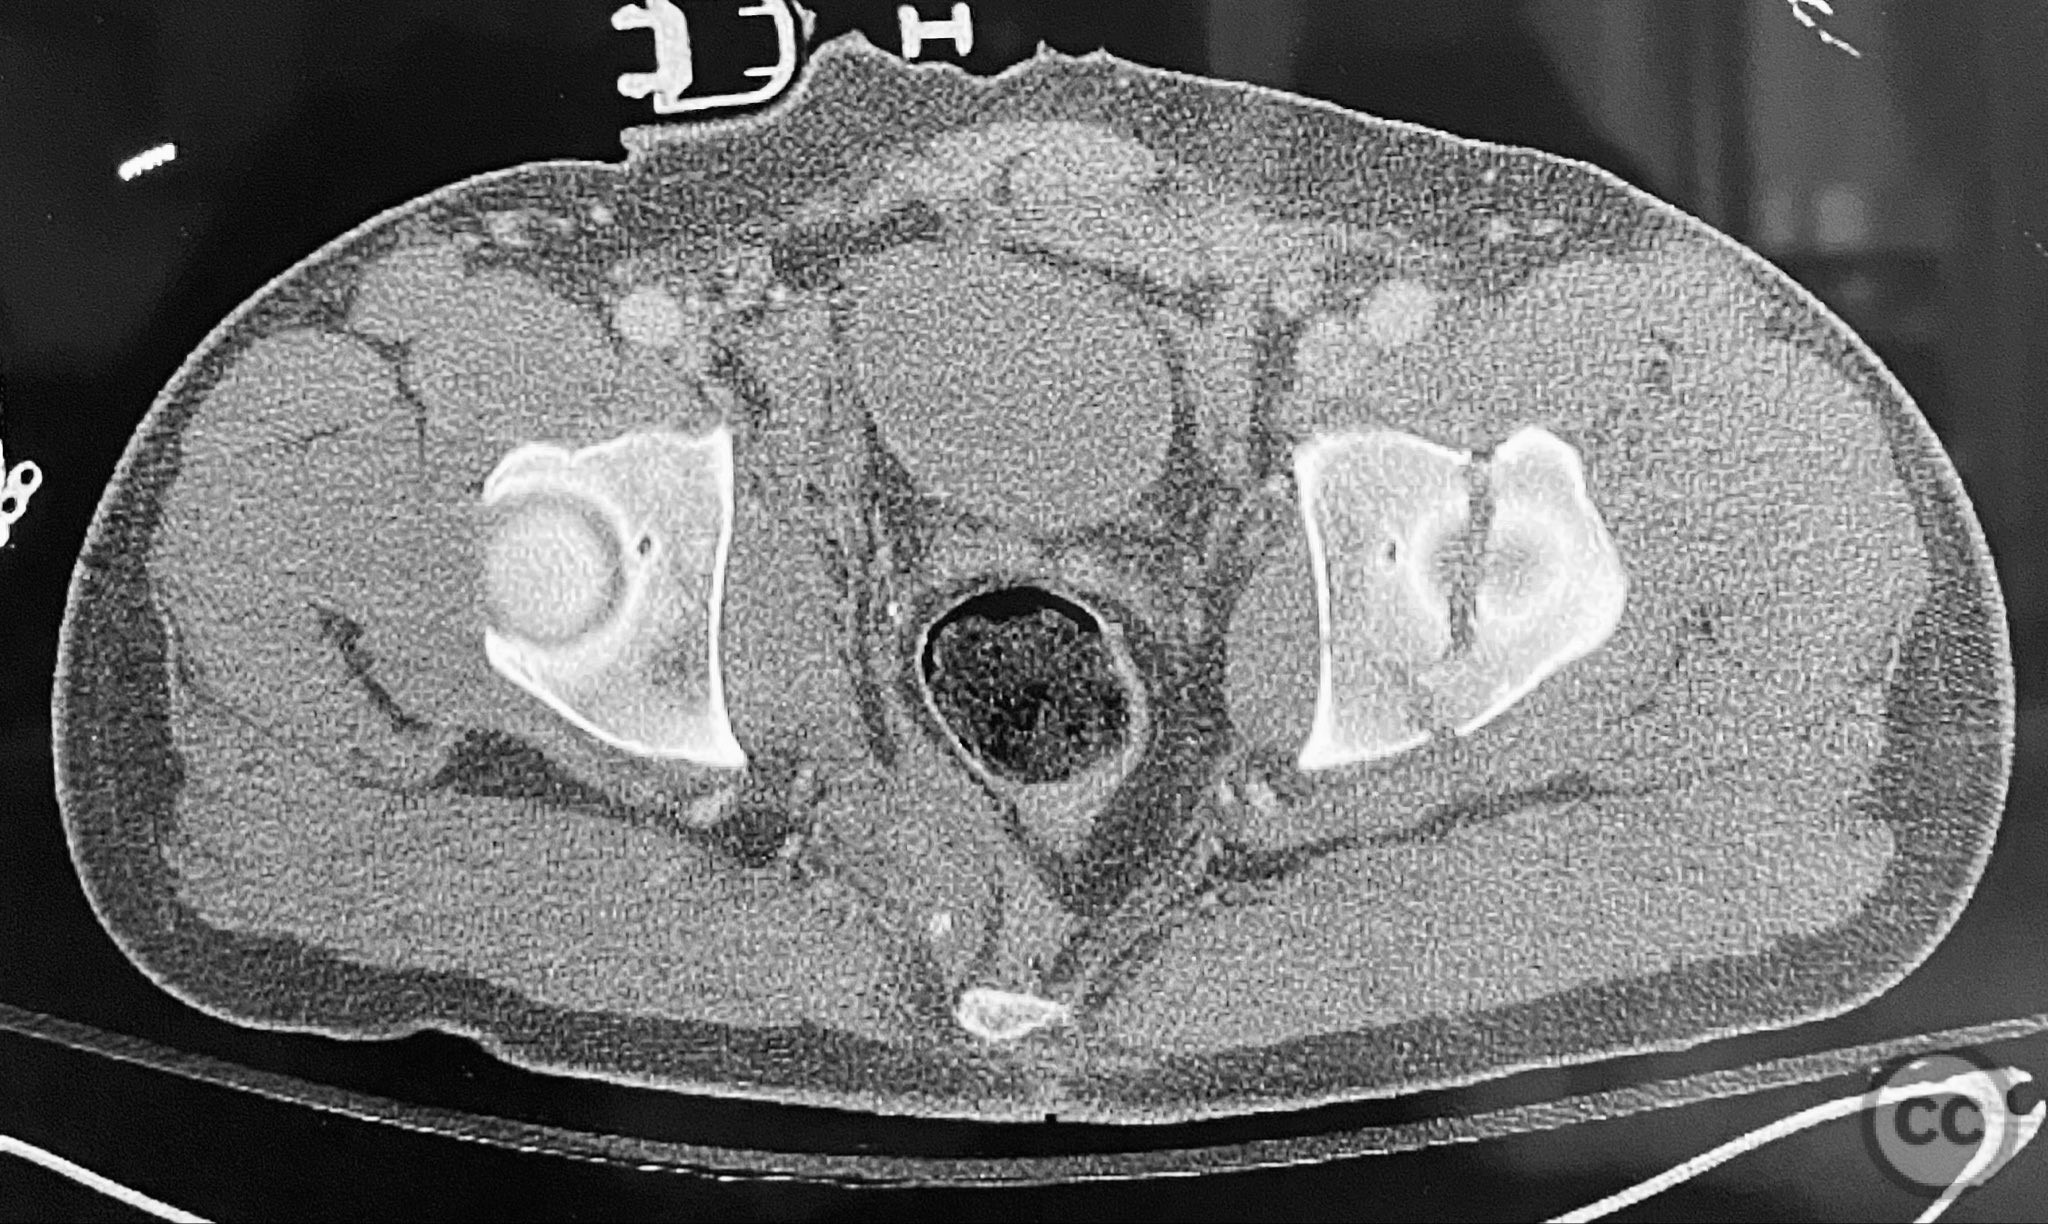

Clinical and radiological findings:  Adult male with a closed, comminuted left femoral shaft fracture and complex pelvic ring injury. Initial imaging demonstrated bilateral sacroiliac (SI) joint disruptions and a left-sided transtectal transverse acetabular fracture (Letournel-Judet: transverse type), with the fracture line exiting through the posterior wall region but without a discrete posterior wall fragment. The femoral head was displaced caudally, following the unstable distal acetabular segment, resulting in loss of congruency with the intact acetabular dome. There was also a symphyseal disruption. No associated abdominal, visceral, thoracic, cranial, or other injuries were present. Application of a circumferential pelvic binder resulted in visible changes in pelvic alignment on imaging. AO/OTA Classification: - Pelvic ring: 61-C1.3 (bilateral SI joint disruption, complete instability) - Acetabulum: 62-B1 (transverse fracture) - Femur: 32-C3 (comminuted diaphyseal fracture)